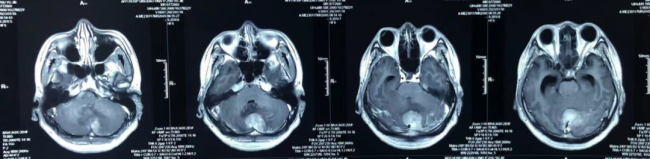

银丰(济南)医院神经肿瘤科团队大胆尝试新药,助力恶性程度4级并已转移扩散的髓母细胞瘤患者重燃希望

2023年1月,23岁的患者朱先生,因头痛就诊于青岛大学附属医院,颅脑磁共振的结果却是命运给他的沉重一击:小脑蚓部占位性病变并幕上阻塞性脑积水。

精准微创除顽疾——银丰(济南)医院神经内镜挑战脊髓播散胶质瘤 “生命禁区”

当胶质瘤从大脑悄然蔓延至脊髓,当患者的生命中枢再次亮起红灯,银丰(济南)医院神经肿瘤科团队毅然迎战。近日,神经肿瘤科科成功完成一例高难度手术:为一位脑胶质瘤术后脊髓播散患者实施神经内镜下微创切除术。